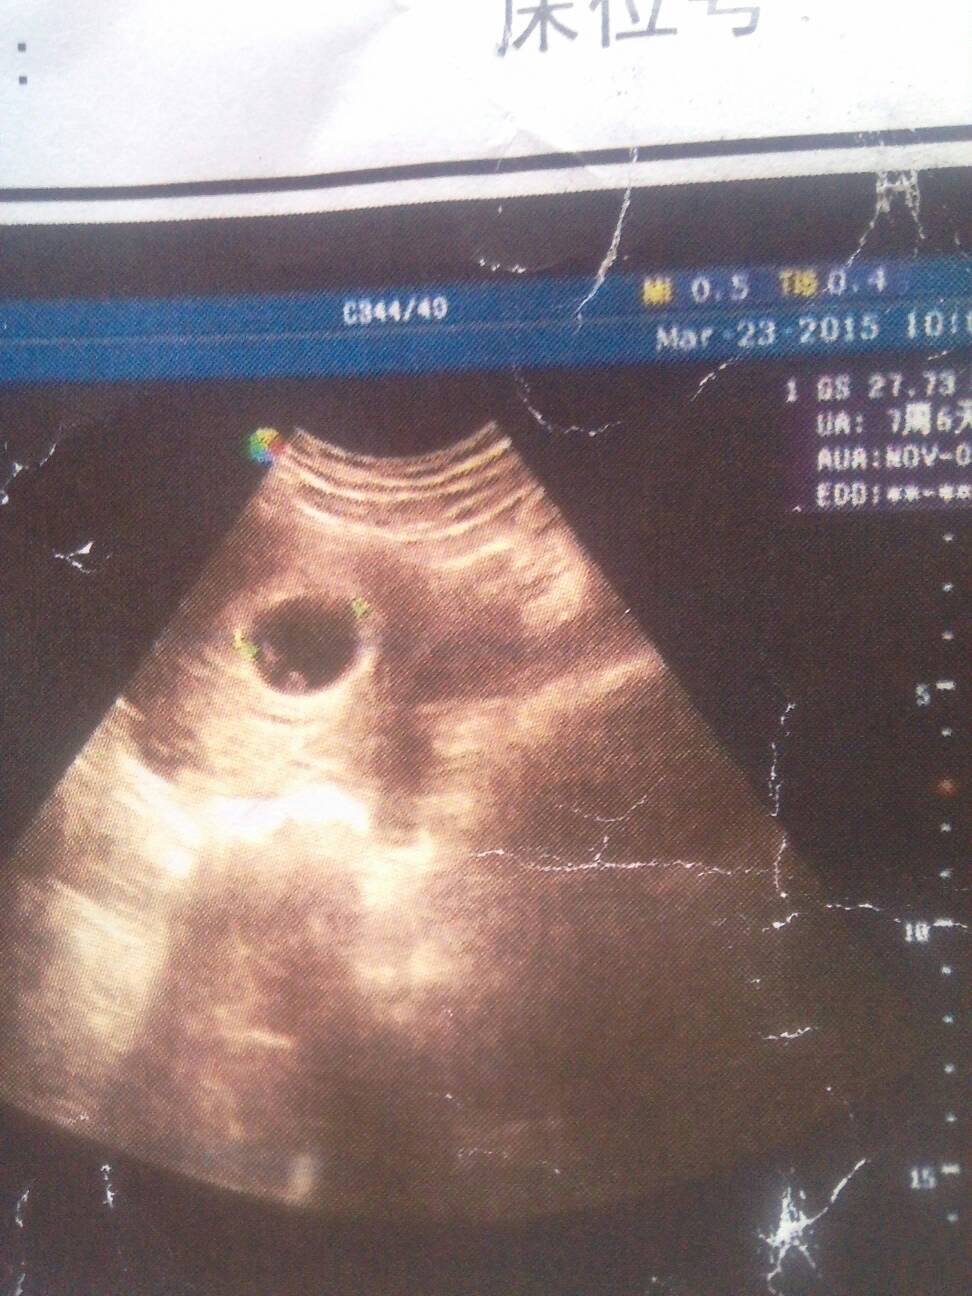

感觉自己像怀双胞胎似的,孕50多天严重吃不下饭恶心干呕!有时头晕的厉害就想吐,只想吃点酸的辣的,做梦梦见的东西都是两个!这是前几天的彩超单帮忙看看

单单这么看像2宝宝,不过不明显

彩超报告单下面是,单头胎就是一个,才50天是感觉不到是不是双胞胎的,喜欢吃酸辣的生女儿

只有一个